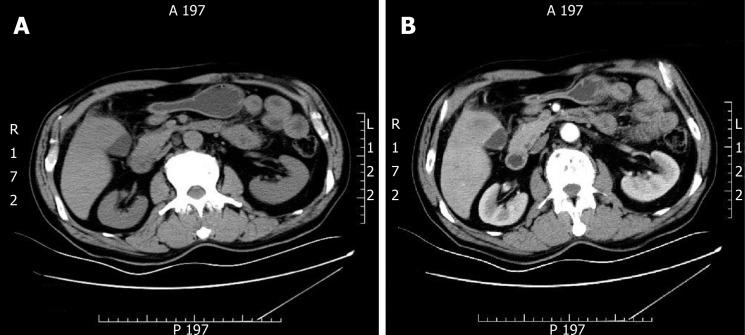

A 64-year-old man was admitted for progressively poor abdominal distension and pain. Liver computed tomography (CT) showed infiltration of gallbladder carcinoma into the adjacent liver, and enlarged retroperitoneal lymph nodes. The patient underwent radical cholecystectomy. Part of the mass was grey and soft, and the neoplastic section showed a purulent-necrotic lesion. Hematoxylin and eosin staining revealed a moderately differentiated SCC. Immunohistochemical studies showed strong staining of the tumor for AE1/3 and CK5/6. Staining for CK19, CK7, and CAM5.2 was positive in the cytoplasm. Systemic chemotherapy was not administered because of the patient's poor physical condition. After five months, CT and magnetic resonance cholangiopancreatography showed multiple metastases in the liver and abdominal cavity.

一名64岁男性因进行性腹胀和腹痛入院。肝脏计算机断层扫描(CT)显示胆囊癌浸润至邻近肝脏,腹膜后淋巴结肿大。患者接受了根治性胆囊切除术。部分肿块呈灰白色且质地柔软,肿瘤切片显示为脓性坏死病变。苏木精-伊红染色显示为中分化鳞状细胞癌。免疫组织化学研究显示肿瘤细胞对AE1/3和CK5/6呈强阳性染色。CK19、CK7和CAM5.2在细胞质中呈阳性染色。由于患者身体状况较差,未进行全身化疗。五个月后,CT和磁共振胰胆管造影显示肝脏和腹腔内有多处转移。